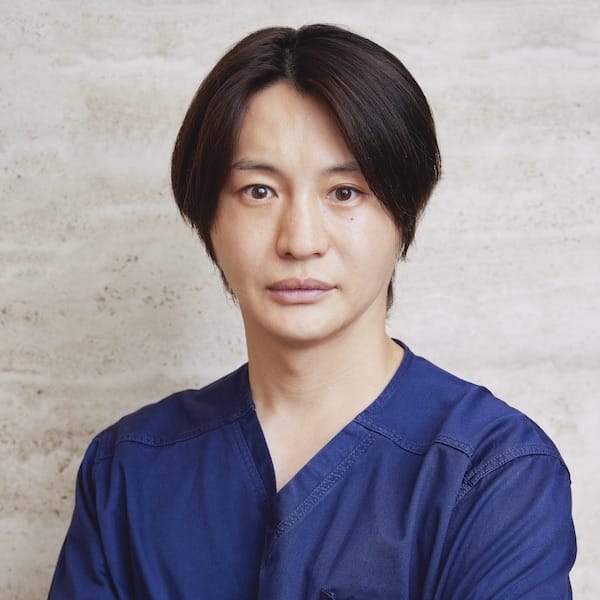

監修・執筆

| 医療法人社団さとうDC 理事長佐藤悠野

当コラムは2020年5月15日に医療法人社団さとうDC 理事長の佐藤悠野が執筆しました。 本文の内容を無断で転載することを禁止します。 |